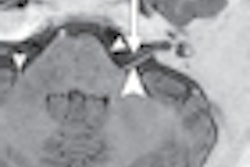

| Functional MRI shows activation maps of one-, two-, and three-back results upon initial scan and at six-week follow-up. Improvement in the working memory circuitry was noted in the follow-up study, which was greater during two-back > one-back conditions (arrows), but less notable with three-back > two-back conditions. All images courtesy of Radiology. |

While the control subjects were able to increase the activity of their working memory circuitry to perform the numbers tasks, the mild traumatic brain injury patients found it more difficult to do so with the moderate and high working load conditions.

The group also noted, however, that the mild traumatic brain injury patients exhibited more activity in some areas outside and inside the working memory circuitry compared to the control subjects. Furthermore, in the six-week follow-up study, MTBI patients showed improved activation in response to greater working memory loads.